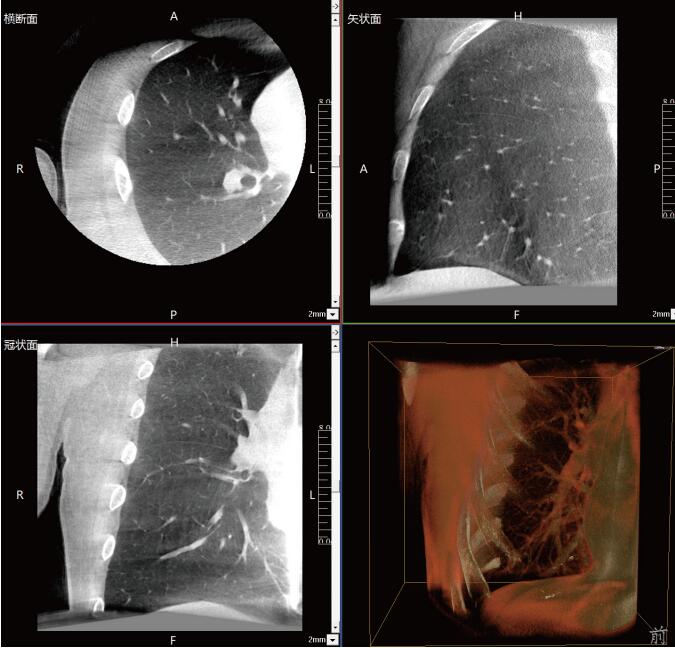

近年來,在肺部手術(shù)領(lǐng)域的應(yīng)用呈現(xiàn)出顯著的增長(zhǎng)態(tài)勢(shì)。這一技術(shù)不僅滿足了臨床指導(dǎo)穿刺、精準(zhǔn)確認(rèn)病變與針尖位置關(guān)系的迫切需求,更通過大量臨床研究的驗(yàn)證,證明了其在肺結(jié)節(jié)診斷、定位及治療中的有效性和安全性。

《中國(guó)專家對(duì)CBCT引導(dǎo)下肺結(jié)節(jié)的診斷、定位和治療的共識(shí)》提到C型臂CT系統(tǒng)憑借其強(qiáng)大的功能,能夠充分滿足透視監(jiān)測(cè)、病變與工具位置確認(rèn)、消融區(qū)監(jiān)測(cè)以及并發(fā)癥檢查等多元化的臨床需求。因此,在考慮設(shè)施條件(如導(dǎo)航設(shè)備、手術(shù)室空間)、靶病灶特性(大小、密度)、麻醉方法及干預(yù)路徑(經(jīng)支氣管或經(jīng)胸)等多重因素的基礎(chǔ)上,C型臂CT系統(tǒng)成為了眾多醫(yī)療機(jī)構(gòu)的優(yōu)選方案。

呼吸介入C型臂CT的臨床適應(yīng)癥廣泛,包括支氣管鏡檢查、肺結(jié)節(jié)穿刺活檢、肺結(jié)節(jié)定位、肺結(jié)節(jié)消融以及經(jīng)支氣管肺結(jié)節(jié)診療等多個(gè)領(lǐng)域。其臨床應(yīng)用價(jià)值不言而喻:在經(jīng)支氣管干預(yù)肺結(jié)節(jié)時(shí),透視功能可精準(zhǔn)引導(dǎo)支氣管鏡與活檢鉗直達(dá)靶結(jié)節(jié);重建的三維圖像則能清晰展示干預(yù)工具的位置,確保操作的準(zhǔn)確性。在肺結(jié)節(jié)消融過程中,呼吸介入C型臂CT更是實(shí)現(xiàn)了高精度定位,有效提升了治療效果。